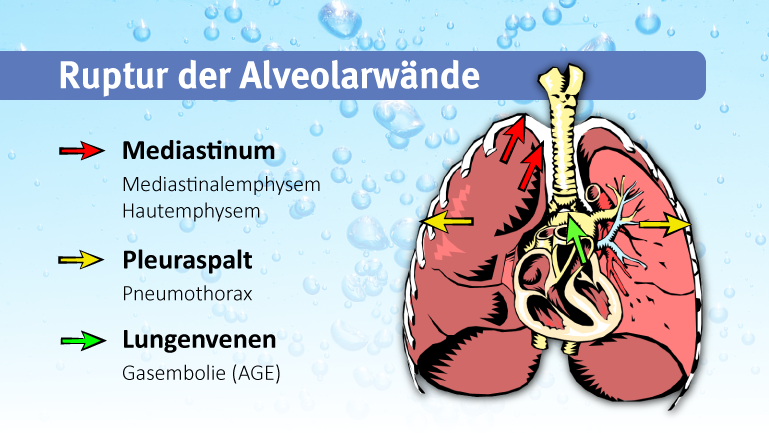

Ein Austreten von Luft kann sich auf unterschiedliche Weisen manifestieren, je nachdem, wo sich der Lungenriss anatomisch befindet. Ein Austreten von Luft in den Brustkorb wird als Pneumothorax bezeichnet. Wenn die Luft in den Herzbeutel oder in den das Herz umgebenden Raum (Mediastinum) entweicht, kann es zu einem sogenannten Pneumoperikard oder Mediastinalemphysem kommen. Wandert die Luft unter die Haut entsteht ein Hautemphysem (meist im Schulter-/Halsbereich). Tritt die Luft in Blutgefäße über spricht man von einer Gasembolie.